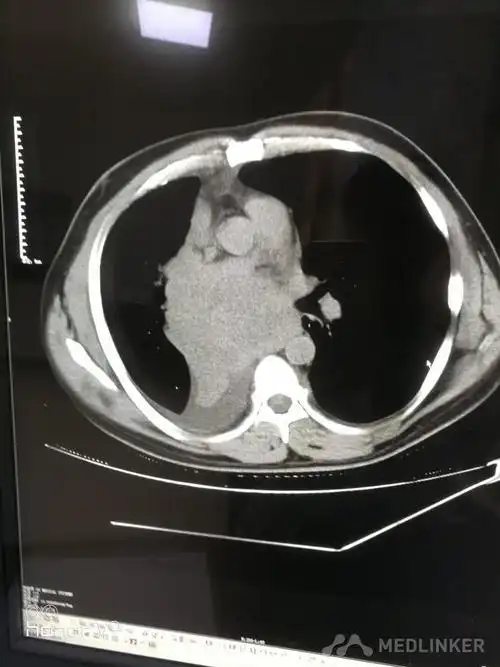

右肺中央型肺癌